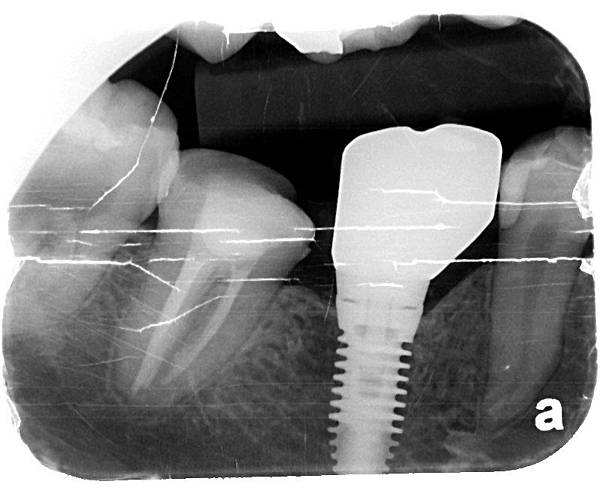

X光片系列

X光片系列

完成圖與一年後追蹤

完成圖 X光片系列

X光片系列